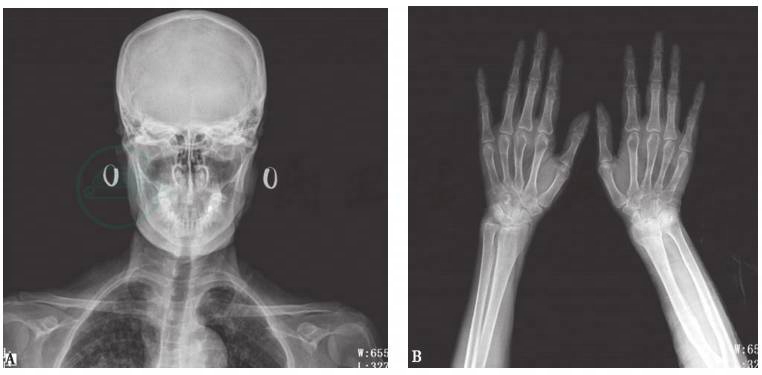

头颅、双手X线平片:骨质疏松(图6)。

图6 头颅、双手X线平片

X线平片可见头颅(A)和双手(B)骨质疏松

引自:主编:.呼吸系统疑难病例诊疗辨析.第1版.ISBN:978-7-117-26415-0